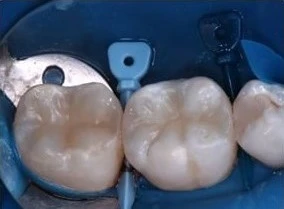

Такие микропротезы можно ставить на жевательные зубы. Часто их используют для установки на импланты.

Основные этапы установки Е-max: